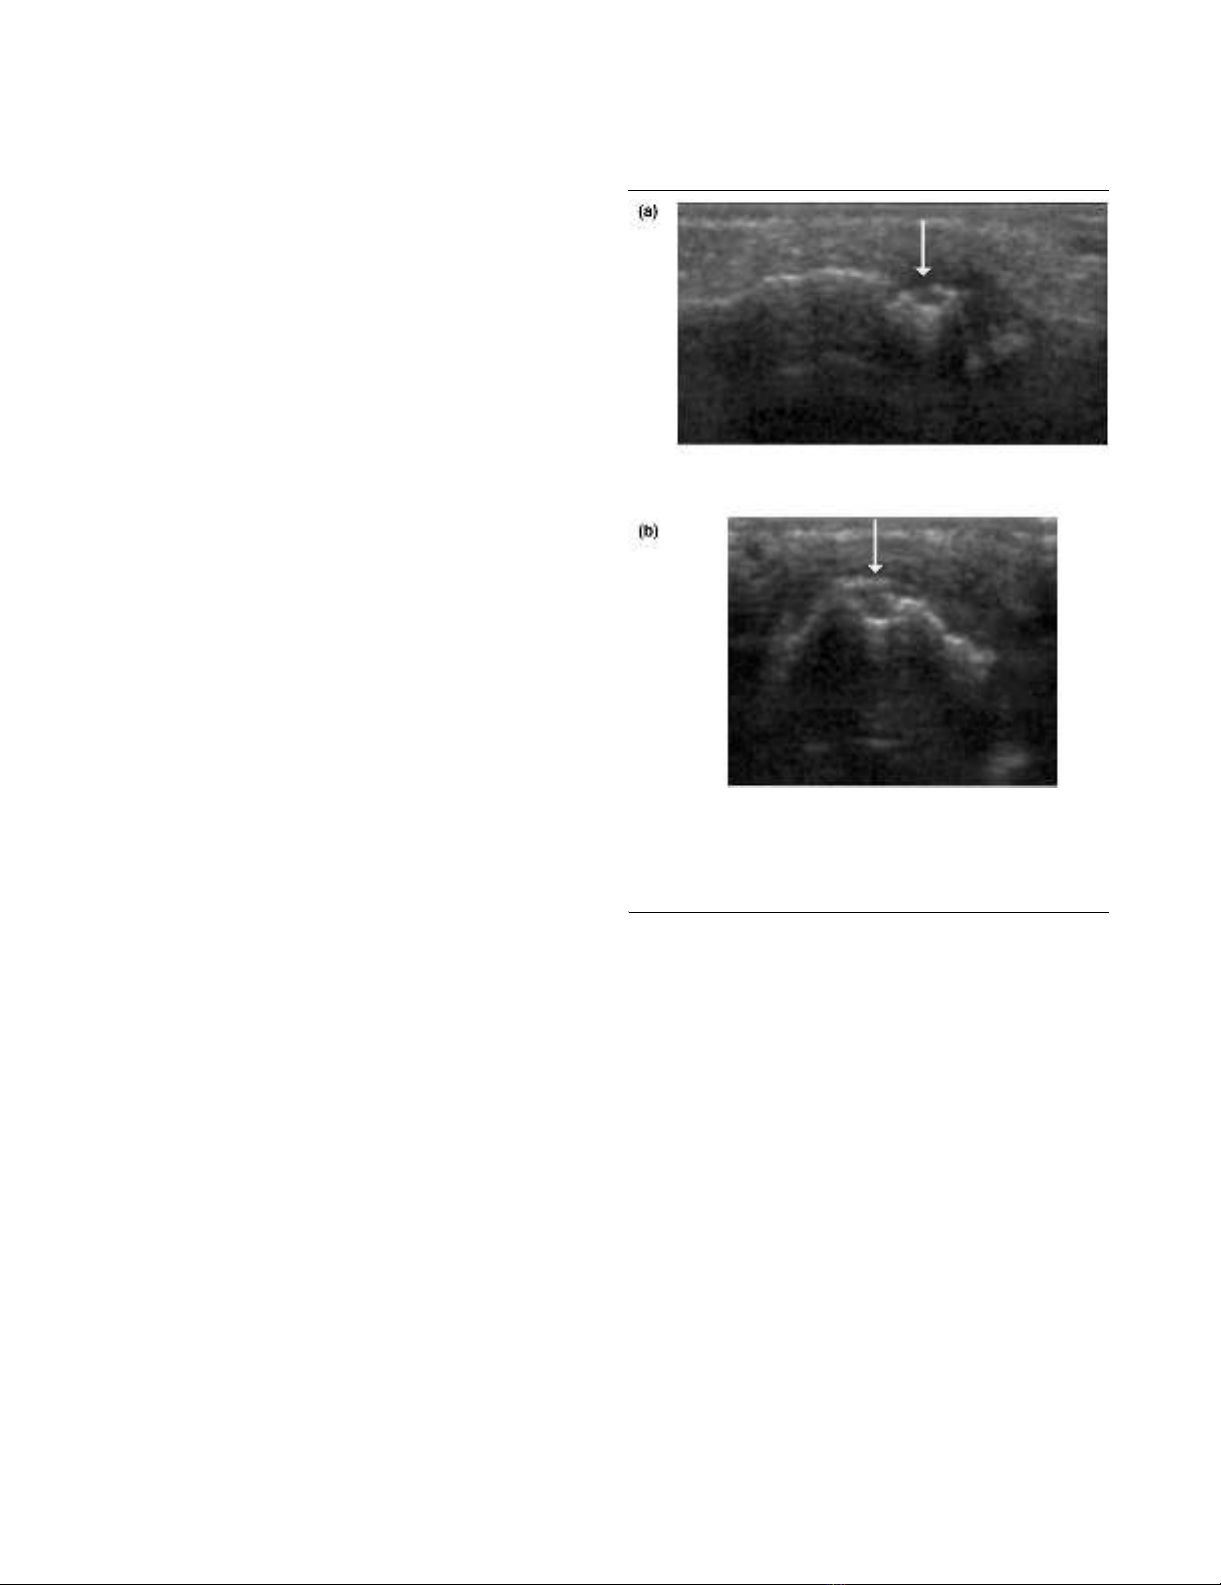

Figure 1

Signs of destruction on ultrasonography in the fourth proximal inter-phalangeal joint: early RASigns of destruction on ultrasonography in the fourth proximal inter-

phalangeal joint: early RA. MRI and conventional radiography revealed

no signs of destruction in the joint. A bone erosion (arrow) is visualized

with ultrasonography in (a) the longitudinal and (b) the transverse

planes. MRI, magnetic resonance imaging; RA, rheumatoid arthritis.